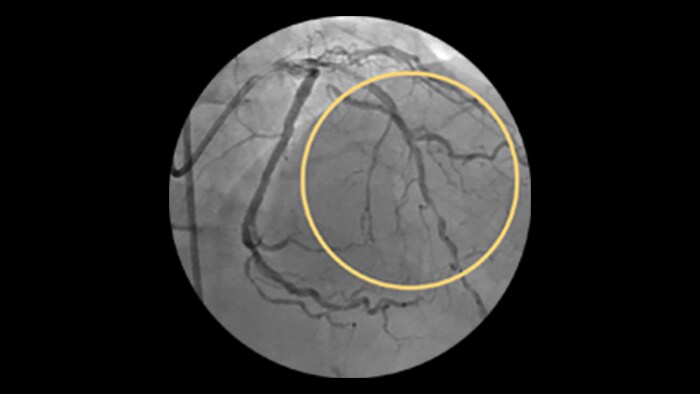

Incidence increases with age, yet older patients are less likely to have PCI attempted.1 Furthermore, 18% of PCIs have a CTO, but less than 5% are being treated.2

IVUS-guided vs. angiography-guided outcomes3